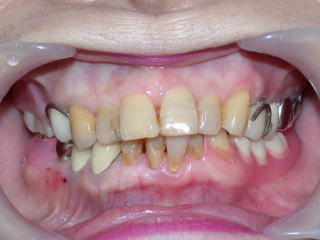

旧義歯、上下顎とも金属ばね使用です。

今回は下顎隆起(外骨症)が大きく、のみピタッとしないので、下顎のみクラスプレスデンチャー作成、装着です。

大きな下顎隆起(外骨)が両側にあります。